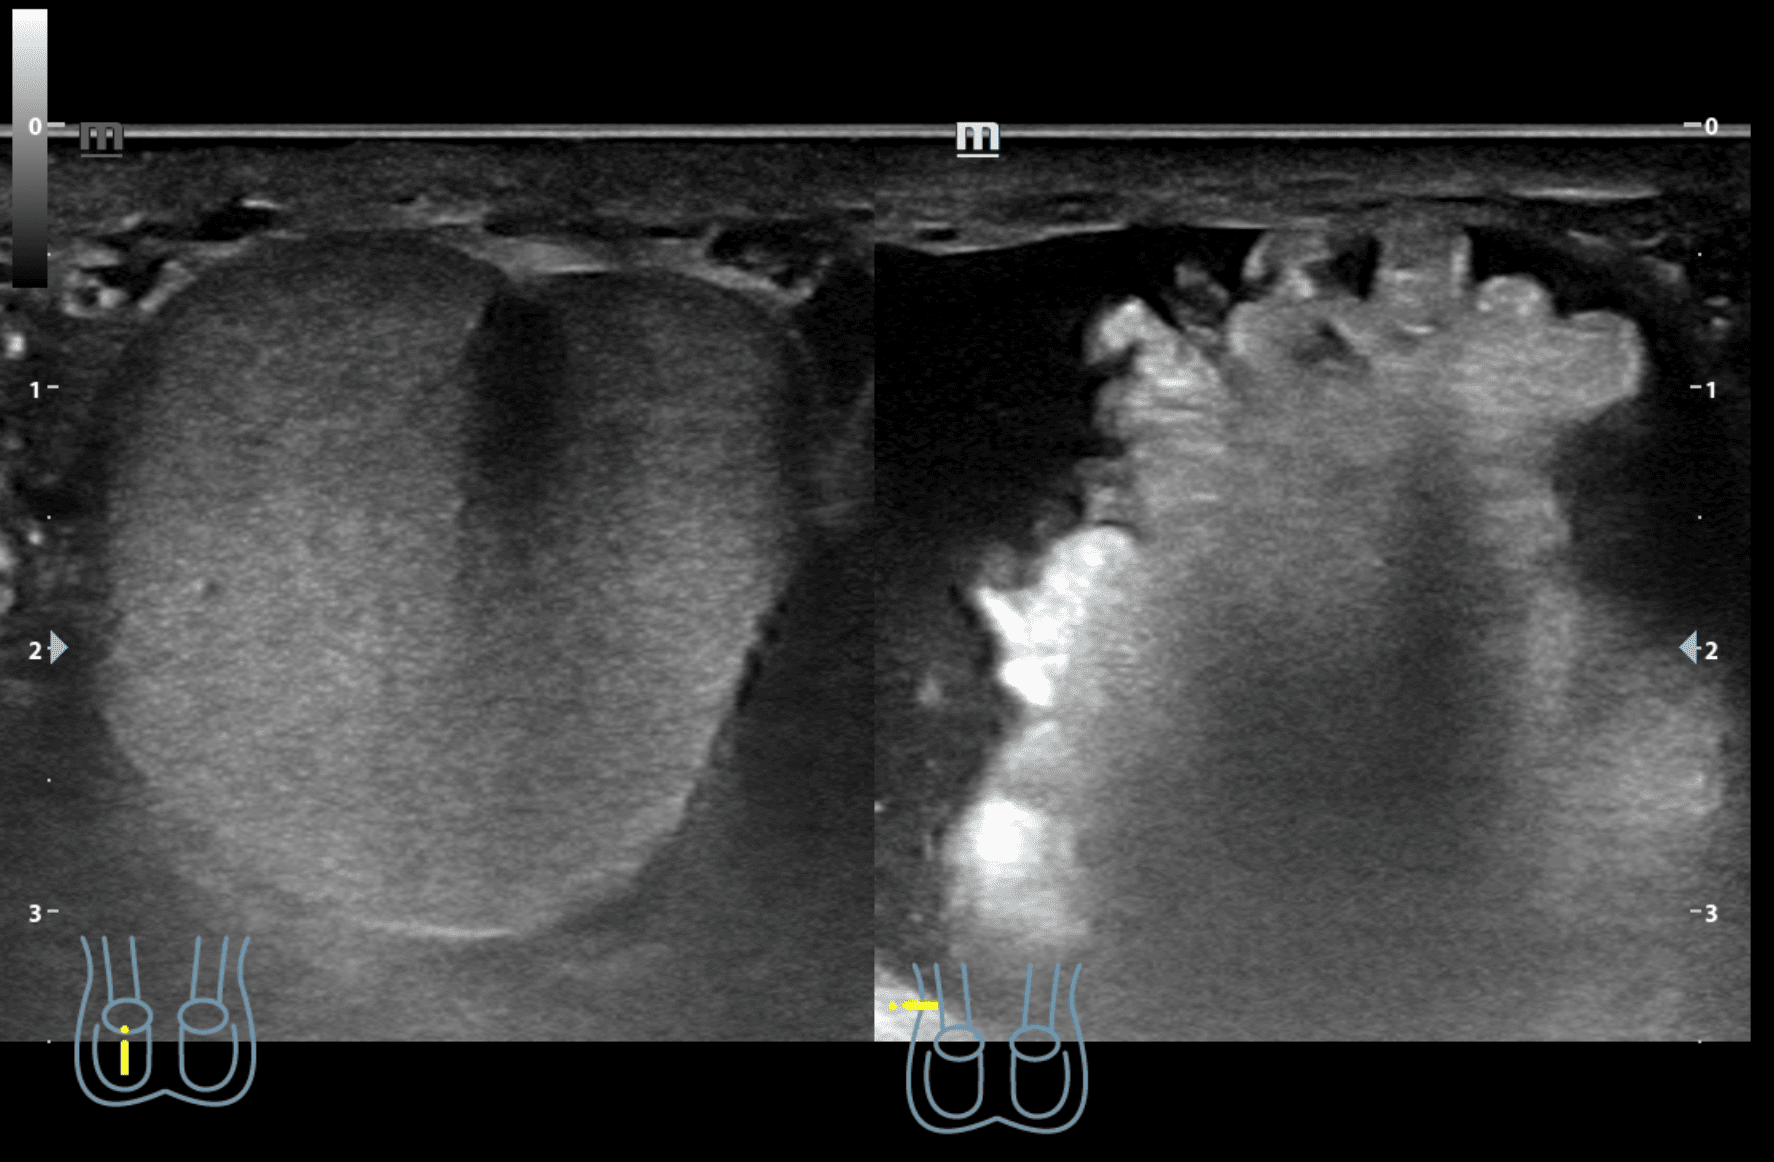

A nivel de escroto derecho, se observa imagen heterogénea con contenido intestinal compatible con hernia inguino-escrotal derecha. Testículos de aspecto normal.

Hernia inguino-escrotal derecha reductible dolorosa, no complicada.